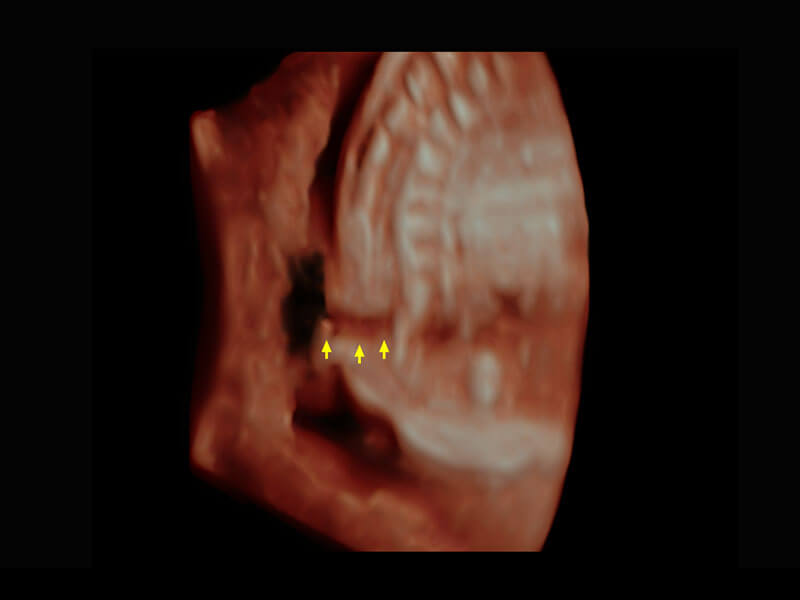

• 右室双出口

• 胎心容积成像